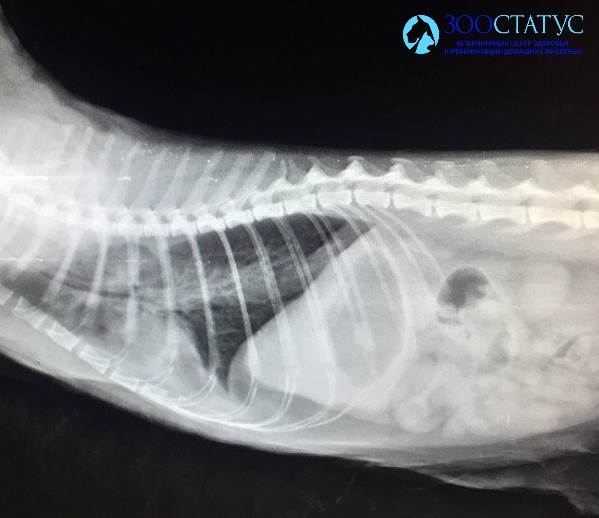

желудочно-кишечного тракта, исключения опухолей, оценки размера и структуры почек - изменения в любом из этих параметров могут стать причиной рвоты. - Рентген – для исключения инородных предметов в

желудочно-кишечном тракте, опухолей, задержки каловых масс как причин рвоты. - Гастроскопия – исследования внутренней поверхности желудка и пищевода, а также взятие анализа тканей стенки желудка для диагностики гастрита, опухолей и язв в желудке, часто сопровождающихся рвотой.